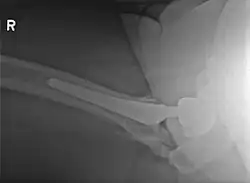

Elbow

• Incidence

• Isolated dislocation: 3-10%

• Dislocation + fracture: 15-20%